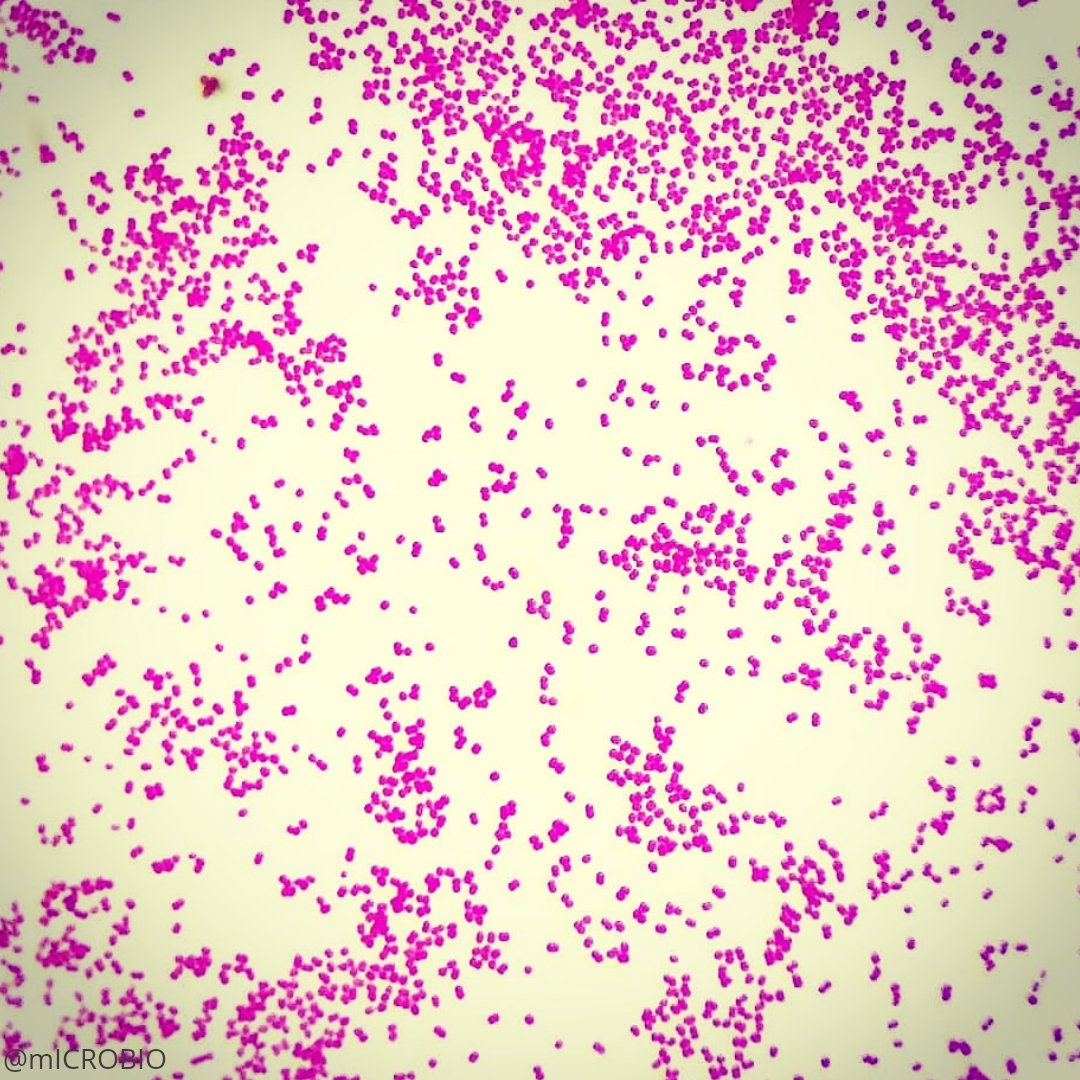

Enfermedades Venéreas 6455 0 Infecciones vaginales VAGINOSIS BACTERIANA Gardnerella vaginalis Por Dr. Mauro VEs importante poder distinguir aquellas infecciones que tienen un origen venéreo, de aquellas que se producen sin que medien relaciones sexuales. Sus manifestaciones más frecuentes son un flujo de color gris y de mal olor, pero sin inflamar las paredes de la vagina. Conozca los síntomas, formas de diagnóstico, cómo afecta a los varones, tratamiento y pronóstico.DAT0S GENERALES La vaginosis bacteriana es una enfermedad que ataca los órganos genitales. No es una enfermedad venérea, pero la hemos incluido porque es una infección vaginal más frecuente. Se llama vaginosis porque, a diferencia de las vaginitis, no inflama las paredes de la vagina; solo provoca un flujo grisáceo y de mal olor. ¿Cómo se llama la bacteria que produce la vaginosis bacteriana? Esta enfermedad es producida por varias bacterias; de ellas, la más conocida es la Gardnerella vaginalis, también llamada Haemophilus vaginalis. Esta bacteria pertenece a la familia de los Bifodobacterium. FRECUENCIA La infección por gardnerella es muy frecuente. Afecta predominantemente a las mujeres, y se la considera la principal causa de mal olor vaginal. Algunos autores reportan que hasta un tercio de las embarazadas cursa con esta afección. CONTAGIO ¿Quiénes pueden sufrir una infección por gardnerella? Todas las personas están expuestas a padecer de una vaginosis bacteriana, porque este germen es un habitante normal del cuerpo, que durante toda la vida es inofensivo y ayuda a mantener el nivel bacteriano adecuado. Sin embargo, ante ciertas situaciones, aumenta en número y genera las molestias características. MANIFESTACIONES El Papanicolaou indica que tengo una gardnerella, pero yo no siento molestias. Como hemos mencionado, la gardnerella normalmente está presente en nuestro cuerpo sin que nos percatemos de ella ni de sus beneficios. Esto es muy importante destacarlo, porque es común que se reporte en los exámenes de una persona sana. A pesar de la alarma por parte del paciente, solo se da tratamiento si existen molestias o hay repercusiones físicas. ¿Cuándo aparecen los síntomas? Para que la gardnerella produzca molestias, es necesario un factor desencadenante que disminuya los niveles de unas bacterias llamadas lactobacilos y aumente el nivel de otras bacterias: los anaerobios. En esas condiciones, la gardnerella y otros gérmenes provocan vaginosis bacteriana. Entre los factores desencadenantes más frecuentes están: • Embarazo • Pastillas anticonceptivas • Antibióticos • Ambientes húmedos • Enfermedades debilitantes • Diabetes • Enfermedades de transmisión sexual • Estrés • Higiene inadecuada • Duchas vaginales • Sobrepeso ¿Cuáles son los síntomas en la mujer? El síntoma más evidente de la vaginosis bacteriana es el olor a pescado en el área vaginal. A menudo se acompaña de un flujo grisáceo, espumoso, a veces amarillento, que no irrita ni inflama las paredes vaginales ni los labios mayores y menores. ¿Cuáles son los síntomas en el hombre? En la práctica diaria, es excepcional ver molestias por gardnerella en varones. Tal vez eso se deba a que el varón es resistente, o a que la bacteria cursa sin síntomas ni molestias en los hombres, o a que todavía desconocemos las repercusiones y manifestaciones en el sexo masculino. En varones con problemas en las defensas, como los pacientes con sida, esta infección provoca ardor en el caño de la orina y una secreción grisácea con olor a pescado. LA INFECCION POR GARDNERELLA Y EMBARAZO ¿La vaginosis bacteriana afecta el curso del embarazo? Clásicamente, se ha descrito que la gardnerella no daña el curso del embarazo . ¿Cómo se sabe si una mujer embarazada tiene vaginosis por gardnerella? El diagnóstico de vaginosis por gardnerella durante el embarazo se realiza con los mismos métodos que se utilizan en mujeres no embarazadas. El examen físico es la forma más usada para efectuar el diagnóstico. ¿La mujer embarazada que tiene gardnerella recibe el tratamiento durante el embarazo o posteriormente? Este es una decisión que toma el médico. En la actualidad existen medicamentos que se pueden emplear durante el embarazo, por lo cual algunos autores recomiendan implementar el tratamiento apenas se cuenta con el diagnóstico. DIAGNOSTICO ¿Cómo se diagnostica la gardnerella? El diagnóstico suele ser muy simple. En general, los médicos estamos entrenados para realizar el diagnóstico con el simple examen físico, sin realizar ningún examen especial. En caso de duda se puede efectuar un frotis, que consiste en tomar una muestra y analizarla al microscopio. También se puede realizar un cultivo. Existe adicionalmente una prueba sencilla: se agrega hidróxido de potasio a una muestra de la secreción; si la gardnerella está presente, despedirá un olor a pescado característico. ¿Existe alguna prueba en sangre? No existe forma de determinar la presencia de gardnerella realizando pruebas sanguíneas. Sin embargo, por lo noble de la enfermedad y lo simple del tratamiento, no resulta necesaria. TRATAMIENTO ¿Cuál es el tratamiento? El tratamiento es sumamente sencillo y existen diversas presentaciones. Se puede tratar con medicamentos tomados, óvulos y cremas. Cuando el episodio de molestias es aislado y único, se tiende a usar los óvulos y las cremas. En caso de recurrencia, es mejor utilizar los tratamientos vía oral y realizar estudios más profundos para detectar si hay alguna infección agregada de fondo. COMPLICACIONES ¿Cuáles son las complicaciones si no se instaura el tratamiento? Es muy raro que una vaginosis evolucione de manera tórpida y provoque cuadros mayores. Cuando esto ocurre, suele ser en pacientes debilitados, como los que padecen de sida. PREVENCION ¿Cómo se pueden prevenir nuevos cuadros de vaginosis bacteriana? Para evitar los episodios constantes y recurrentes, es fundamental determinar cuál factor está desencadenando la infección por gardnerella. Si es una diabetes, procede un mejor control en los niveles de azúcar. Si es una enfermedad venérea de fondo, se debe tratar de manera exhaustiva, y así sucesivamente con cada factor desencadenante. ¿El preservativo es eficaz para evitar los cuadros de vaginosis bacteriana? Como esta infección no es una enfermedad venérea, las relaciones sexuales no juegan un papel estelar. En algunos casos el semen puede desencadenar una vaginosis bacteriana, situación en la que está indicado el uso del preservativo. Si una persona presenta una vaginosis por gardnerella, ¿está protegida de un nuevo episodio? Claro que no. La vaginosis suele presentarse en múltiples ocasiones, y no genera inmunidad o protección para un futuro episodio. ¿Existe alguna vacuna para evitar la vaginosis? No existe ninguna vacuna para combatir esta vaginosis. RELACION CON OTRAS ENFERMEDADES ¿La presencia de gardnerella se asocia a la presencia de alguna otra infección? En un inicio, se creyó que la vaginosis bacteriana por gardnerella era una enfermedad de transmisión sexual. Hoy sabemos que no; pero según algunos reportes, es común que se asocie a la presencia de otras infecciones que sí son venéreas. Esta es la razón por la cual algunos estudios recomiendan que en el paciente con vaginosis a repetición o cuando los cuadros no ceden en su totalidad con el tratamiento, se practiquen estudios completos de infecciones sexualmente transmisibles, entre ellas sida, virus del papiloma, herpes genital, hepatitis B, clamidia, gonorrea y sífilis. ¿Hay alguna relación entre el sida y la gardnerella? El paciente con sida presenta con mayor facilidad cuadros recurrentes y recidivantes por gardnerella, y los síntomas suelen ser más intensos y molestos.